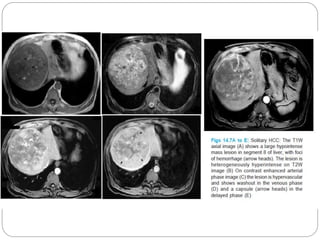

MRI

 Small HCC’s v/s regenerative

 Cirrhotic nodule: hyper on T1 , hypo on T2

 HCC : hypo on T1, hyperintense on T2

HCC arising in a siderotic nodule: “nodule within a

nodule” appearance

HCC - a small focus of high signal intensity

within the low signal intensity nodule(T2).

MRI  Small HCC’sv/s regenerative  Cirrhotic nodule: hyper on T1 , hypo on T2  HCC : hypo on T1, hyperintense on T2 HCC arising in a siderotic nodule: “nodule within a nodule” appearance HCC - a small focus of high signal intensity within the low signal intensity nodule(T2).